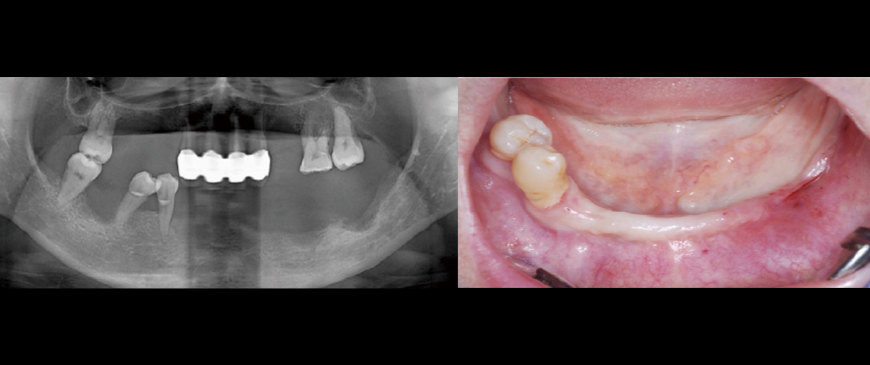

Fig 1

A woman in her late 40s presented with multiple tooth loss and chewing difficulties due to severe periodontal disease. The mandibular anterior region had a thin ridge, but vertical dimension was maintained in both jaws. The upper jaw was to be restored with a partial denture, while the lower jaw was treated with All-on-6 implants to address vertical dimension loss in the left posterior region.

Fig 2

The 2 right premolars were extracted, and a flap raised. Identifying the mental foramen location is key for All-on-X, after which placing tilted implants at 30- 45° completes half the procedure.

Fig 8

Post-surgery panoramic radiograph. Immediately after the surgery, impressions were taken to prepare provisional prostheses.

Fig 9

Post-surgery CBCT radiograph. All ARi implant threaded parts were properly positioned within the alveolar bone

Panoramic image when custom abutments and PMMA bridge were placed.

Fig 12